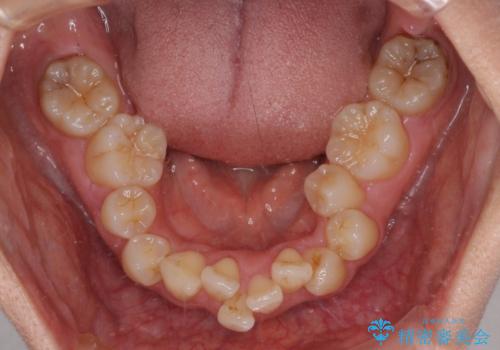

全顎的なデコボコと口元の突出感 ワイヤー装置での抜歯矯正で整った口元に

- 奥歯も含めて全体的なデコボコと前歯の突出感を気にして来院された患者様です。

上下左右第一小臼歯4本を抜歯し、ワイヤー装置にて矯正治療を行うこととしました。

想像以上に咬合力が強く、抜歯したスペースを閉じきるまでに長期間を要することとなりました。

前歯の突出感がなくなり、仕上がりには大変満足していただけました。